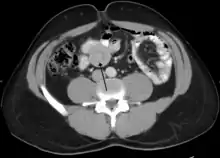

An intussusception is often suspected based on history and physical exam, including observation of Dance's sign. A digital rectal examination is particularly helpful in children, as part of the intussusceptum may be felt by the finger. A definite diagnosis often requires confirmation by diagnostic imaging modalities. Ultrasound is the imaging modality of choice for diagnosis and exclusion of intussusception, due to its high accuracy and lack of radiation. The appearance of target sign (also called "doughnut sign" on a sonograph, usually around 3 cm in diameter, confirms the diagnosis. The image seen on transverse sonography or computed tomography is that of a doughnut shape, created by the hyperechoic central core of bowel and mesentery surrounded by the hypoechoic outer edematous bowel.[11] In longitudinal imaging, intussusception resembles a sandwich.[11] It is also called "pseudokidney" sign because hyperechoic tubular centre is covered by a hypoechoic rim producing a kidney-like appearance.[12]